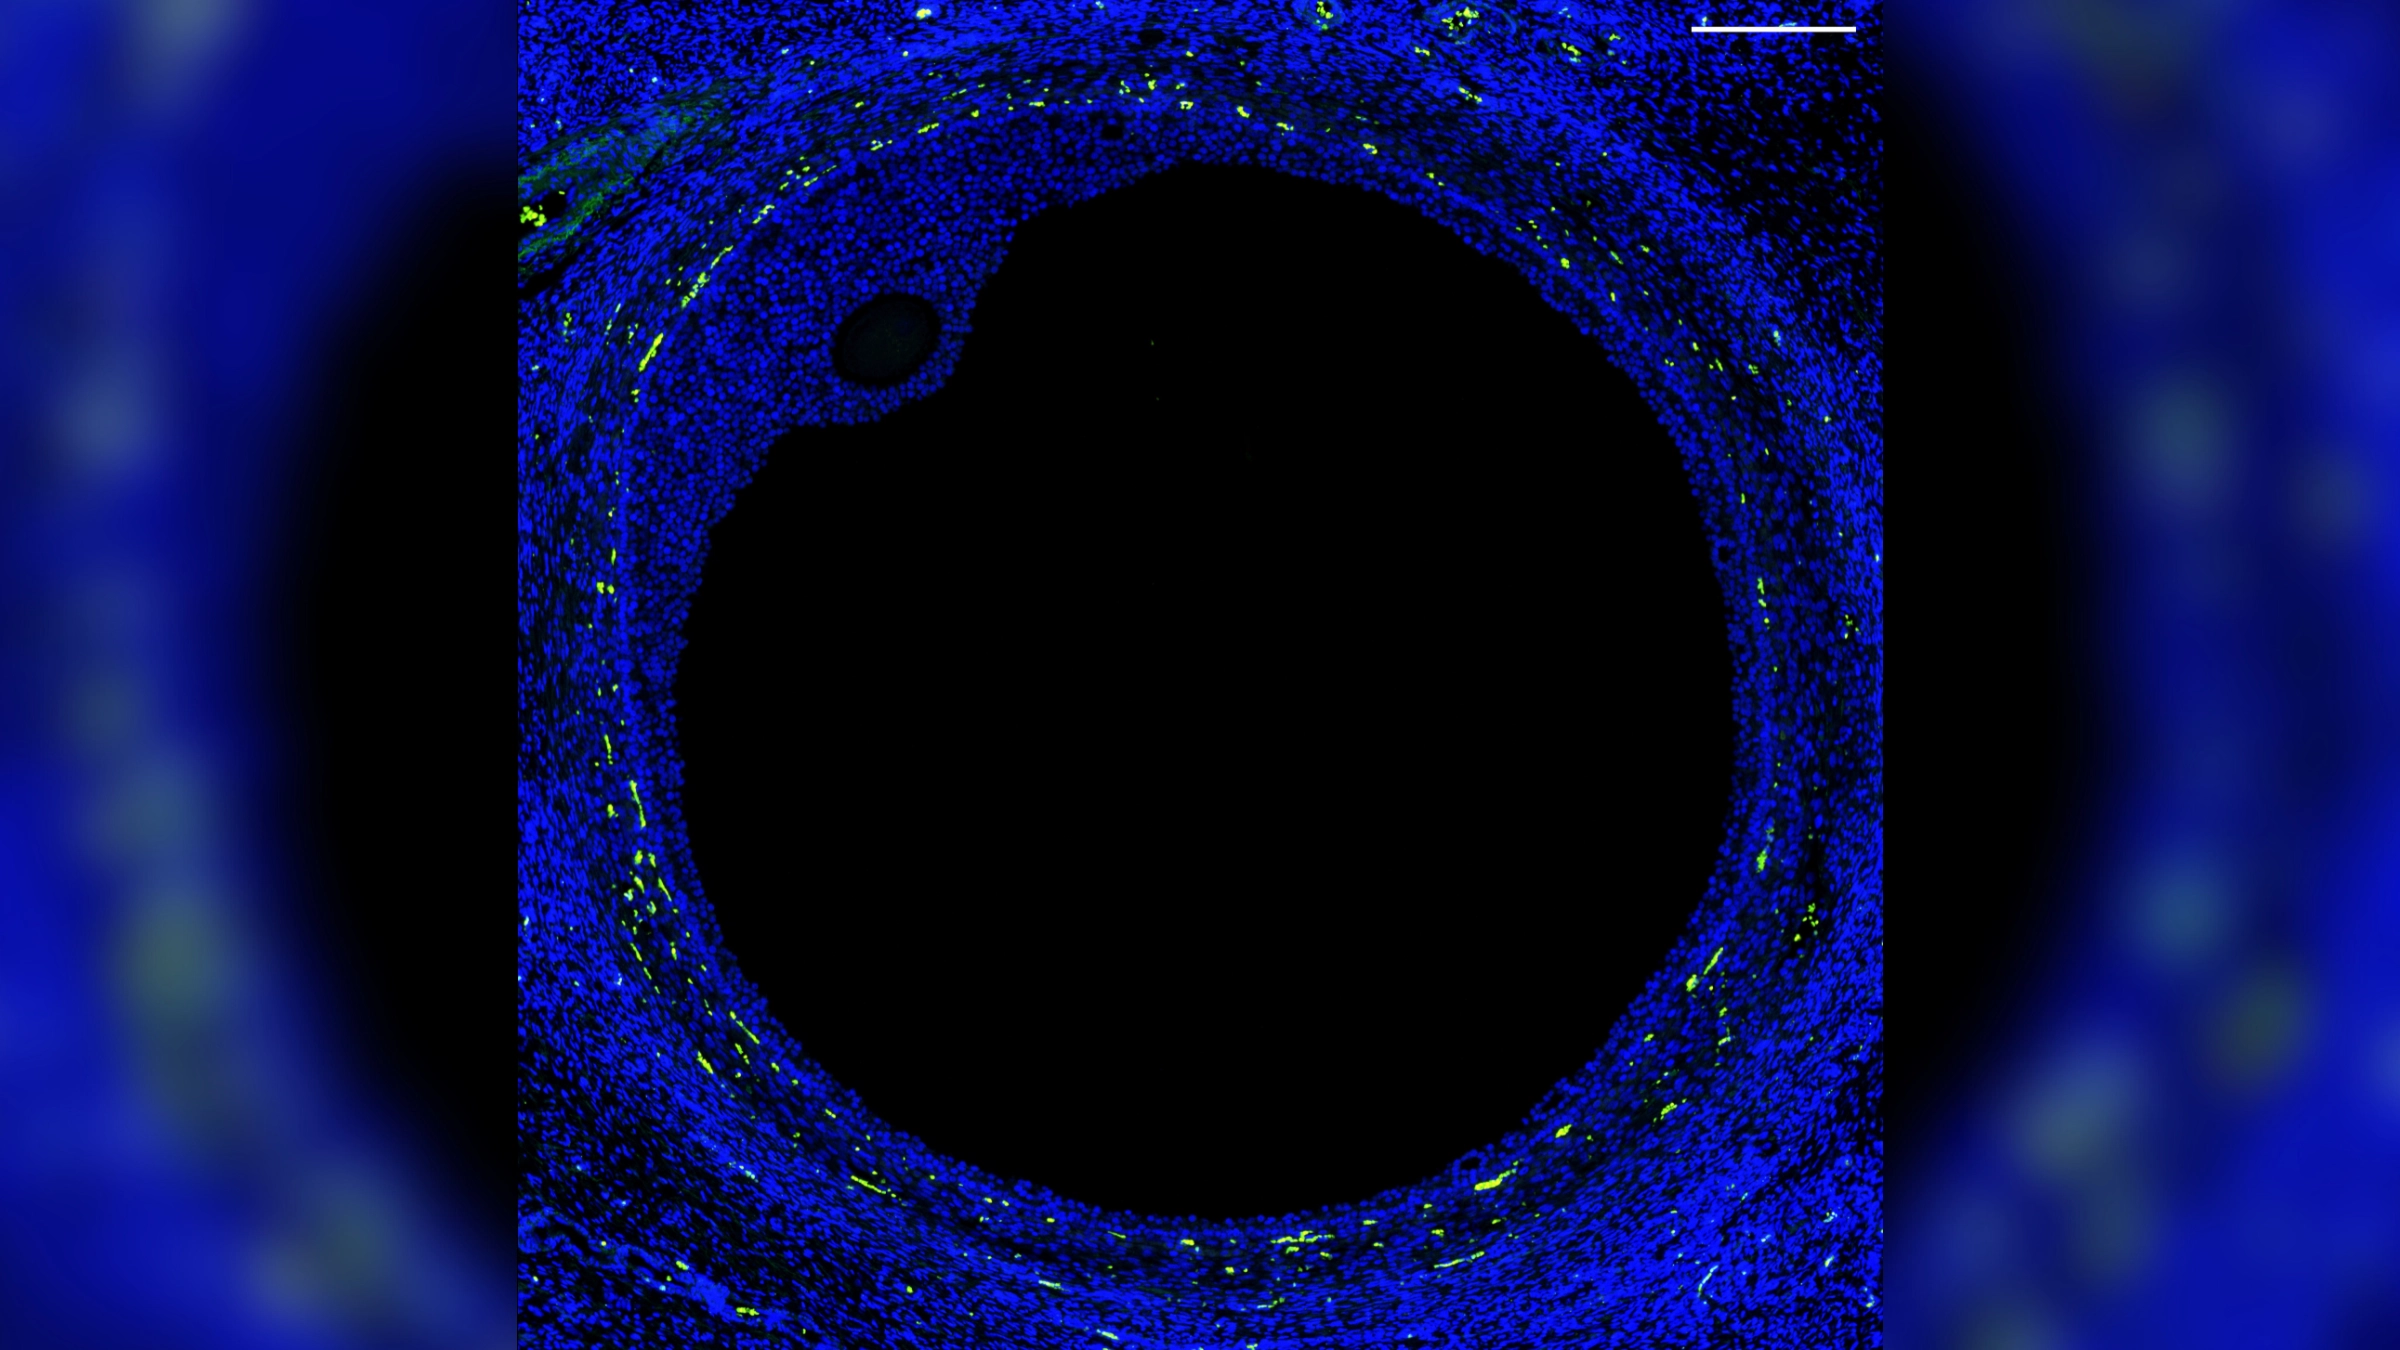

For the first time, scientists have created a comprehensive "atlas" of the cells in the human ovary and mapped the specific pattern of gene activity required for a healthy egg to develop.

The researchers determined which genes are activated in specific cells, and at what points they are activated during normal egg development, by analyzing ovarian tissue from organ donors. The key genes include those that need to be activated within the follicles — tiny sacs that hold developing eggs and release hormones — to produce mature eggs that can then be fertilized by sperm to give rise to a fetus.

To figure out what factors are needed for a follicle to release a fully mature egg, the researchers measured the activity of genes in different ovarian cells in tissue donated from five deceased, reproductive-age women. They did this by analyzing RNA — a type of genetic molecule that is used to make proteins using instructions from DNA — within the tissue.

The researchers identified distinct patterns of gene activity in the major cell types found in developing follicles, such as the oocytes and supportive cells that secrete reproductive hormones.